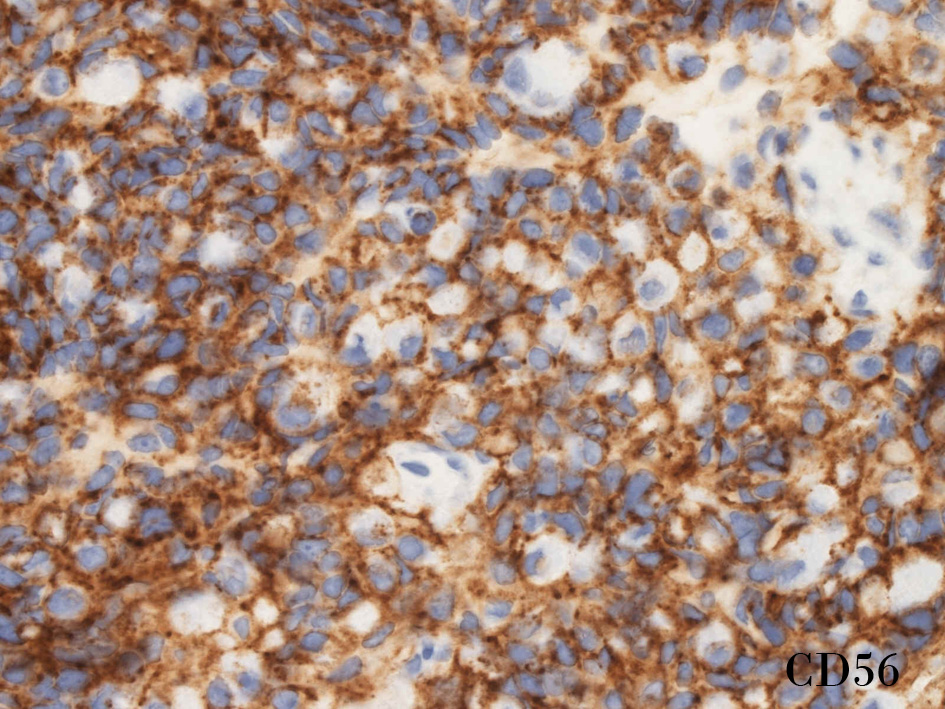

CD56.jpg

CD56rha.jpg

CD56CD56S-100

small round cell tumorの中でrhabdomyosarcomaは腫瘍細胞に種々の抗原が陽性となるため診断を誤ることがあり注意が必要である*1